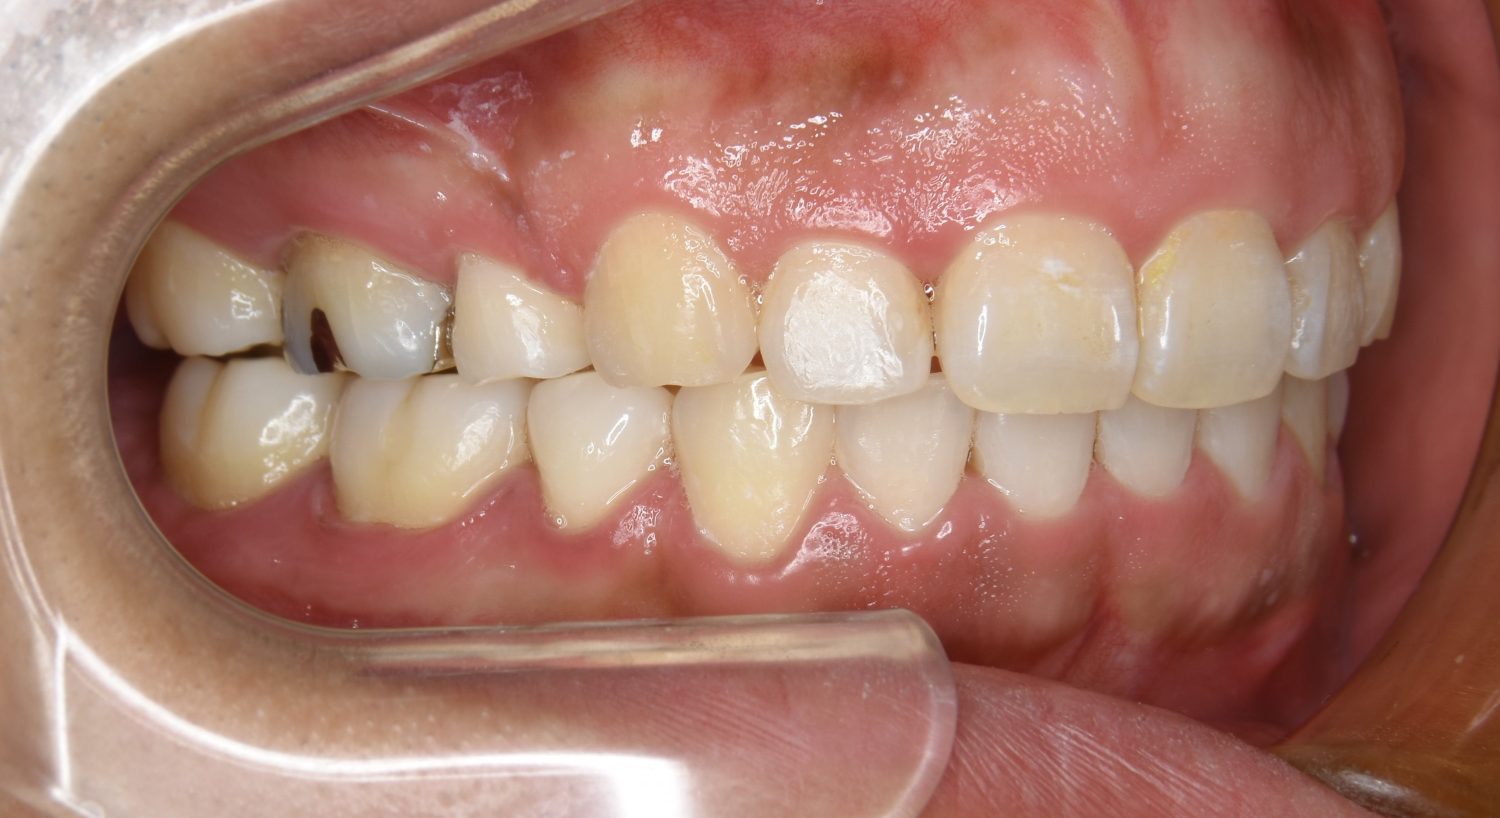

叢生の症例紹介②

Before

After

主訴

歯の凸凹を治したい。

治療内容

アライナー(インビザライン)にて非抜歯で治療を行いました。

治療費

1,150,000 円(税込)

治療期間

26ヶ月

通院回数

14回

想定されたリスク

※歯根吸収、歯肉退縮、歯髄壊死、顎関節症状

※アライナー(インビザライン)は日本の薬機法未承認の矯正装置であり、医薬品副作用被害救済制度の対象外となる場合があります。

丸山和宏先生

ピーススマイル矯正歯科

上下前歯部に叢生(凸凹)が認められる状態でした。歯列の遠心移動を行うことで機能面および審美面が改善されました。